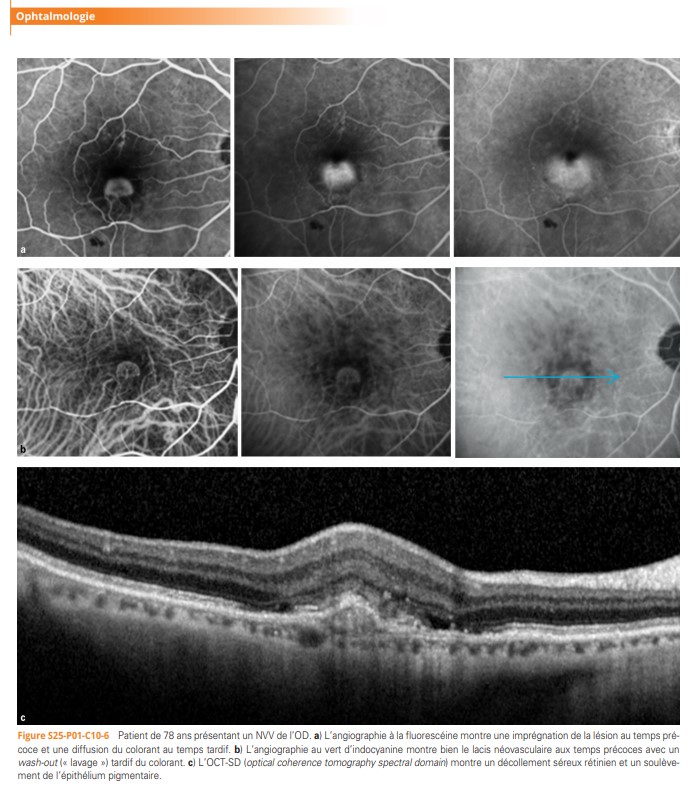

macula (région centrale de la rétine) avec, pour conséquence, une baisse de la vision centrale. Les moyens d’exploration et de suivi des maladies rétiniennes, sont aujourd’hui assurés par l’OCT (optical coherence tomography) et l’angiographie à la fluorescéine et/ou au vert d’indocyanine. L’arsenal thérapeutique des maladies de la rétine s’est aujourd’hui étoffé et comprend les traitements par laser thermique, photothérapie dynamique et injections intravitréennes (anti-vascular endothelial growth factor [VEGF] ou corticoïdes). »